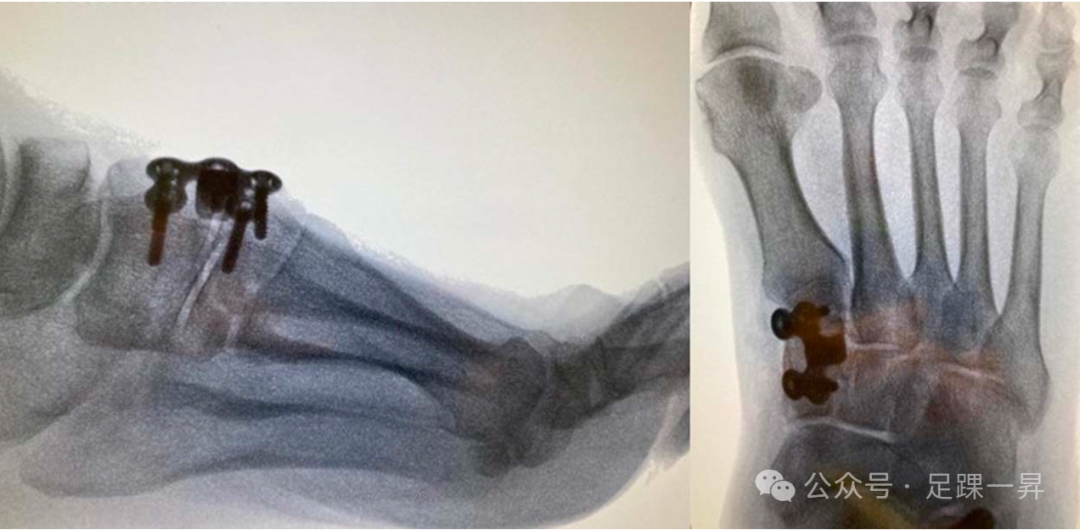

高弓足顾名思义指的是侧面观足弓高企,在行走或者负重过程中过程失去弹性,不能相对变平,从而不能完成正常站立和行走功能。